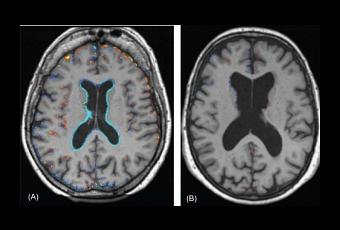

Les premiers résultats de cet essai révèlent que des doses importantes de vitamines B ralentissent de 30% le rythme de l'atrophie cérébrale en comparaison d'un placebo (Voir visuel ci-contre). Sur les 266 personnes qui ont commencé l'étude, 223 (83,8%) l'ont terminée. Les chercheurs constatent que:

Sources:International Journal of Geriatric Psychiatry,July 21 2011 DOI: 10.1002/gps.2758 Cognitive and clinical outcomes of homocysteine-lowering B-vitamin treatment in mild cognitive impairment: a randomized controlled trial.PLoS One5(9): doi:10.1371/journal.pone.0012244 Homocysteine-Lowering by B Vitamins Slows the Rate of Accelerated Brain Atrophy in Mild Cognitive Impairment: A Randomized Controlled Trial. (Visuel PloS ONE A: Placebo, B: Vitamin B)